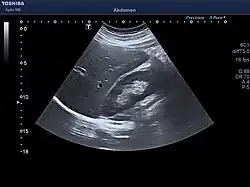

Adult ultrasound showing the right lobe of the liver and right kidney

At birth, the liver comprises roughly 4% of body weight and weighs on average about 120 g (4 oz). Over the course of further development, it will increase to 1.4–1.6 kg (3.1–3.5 lb) but will only take up 2.5–3.5% of body weight.[40]